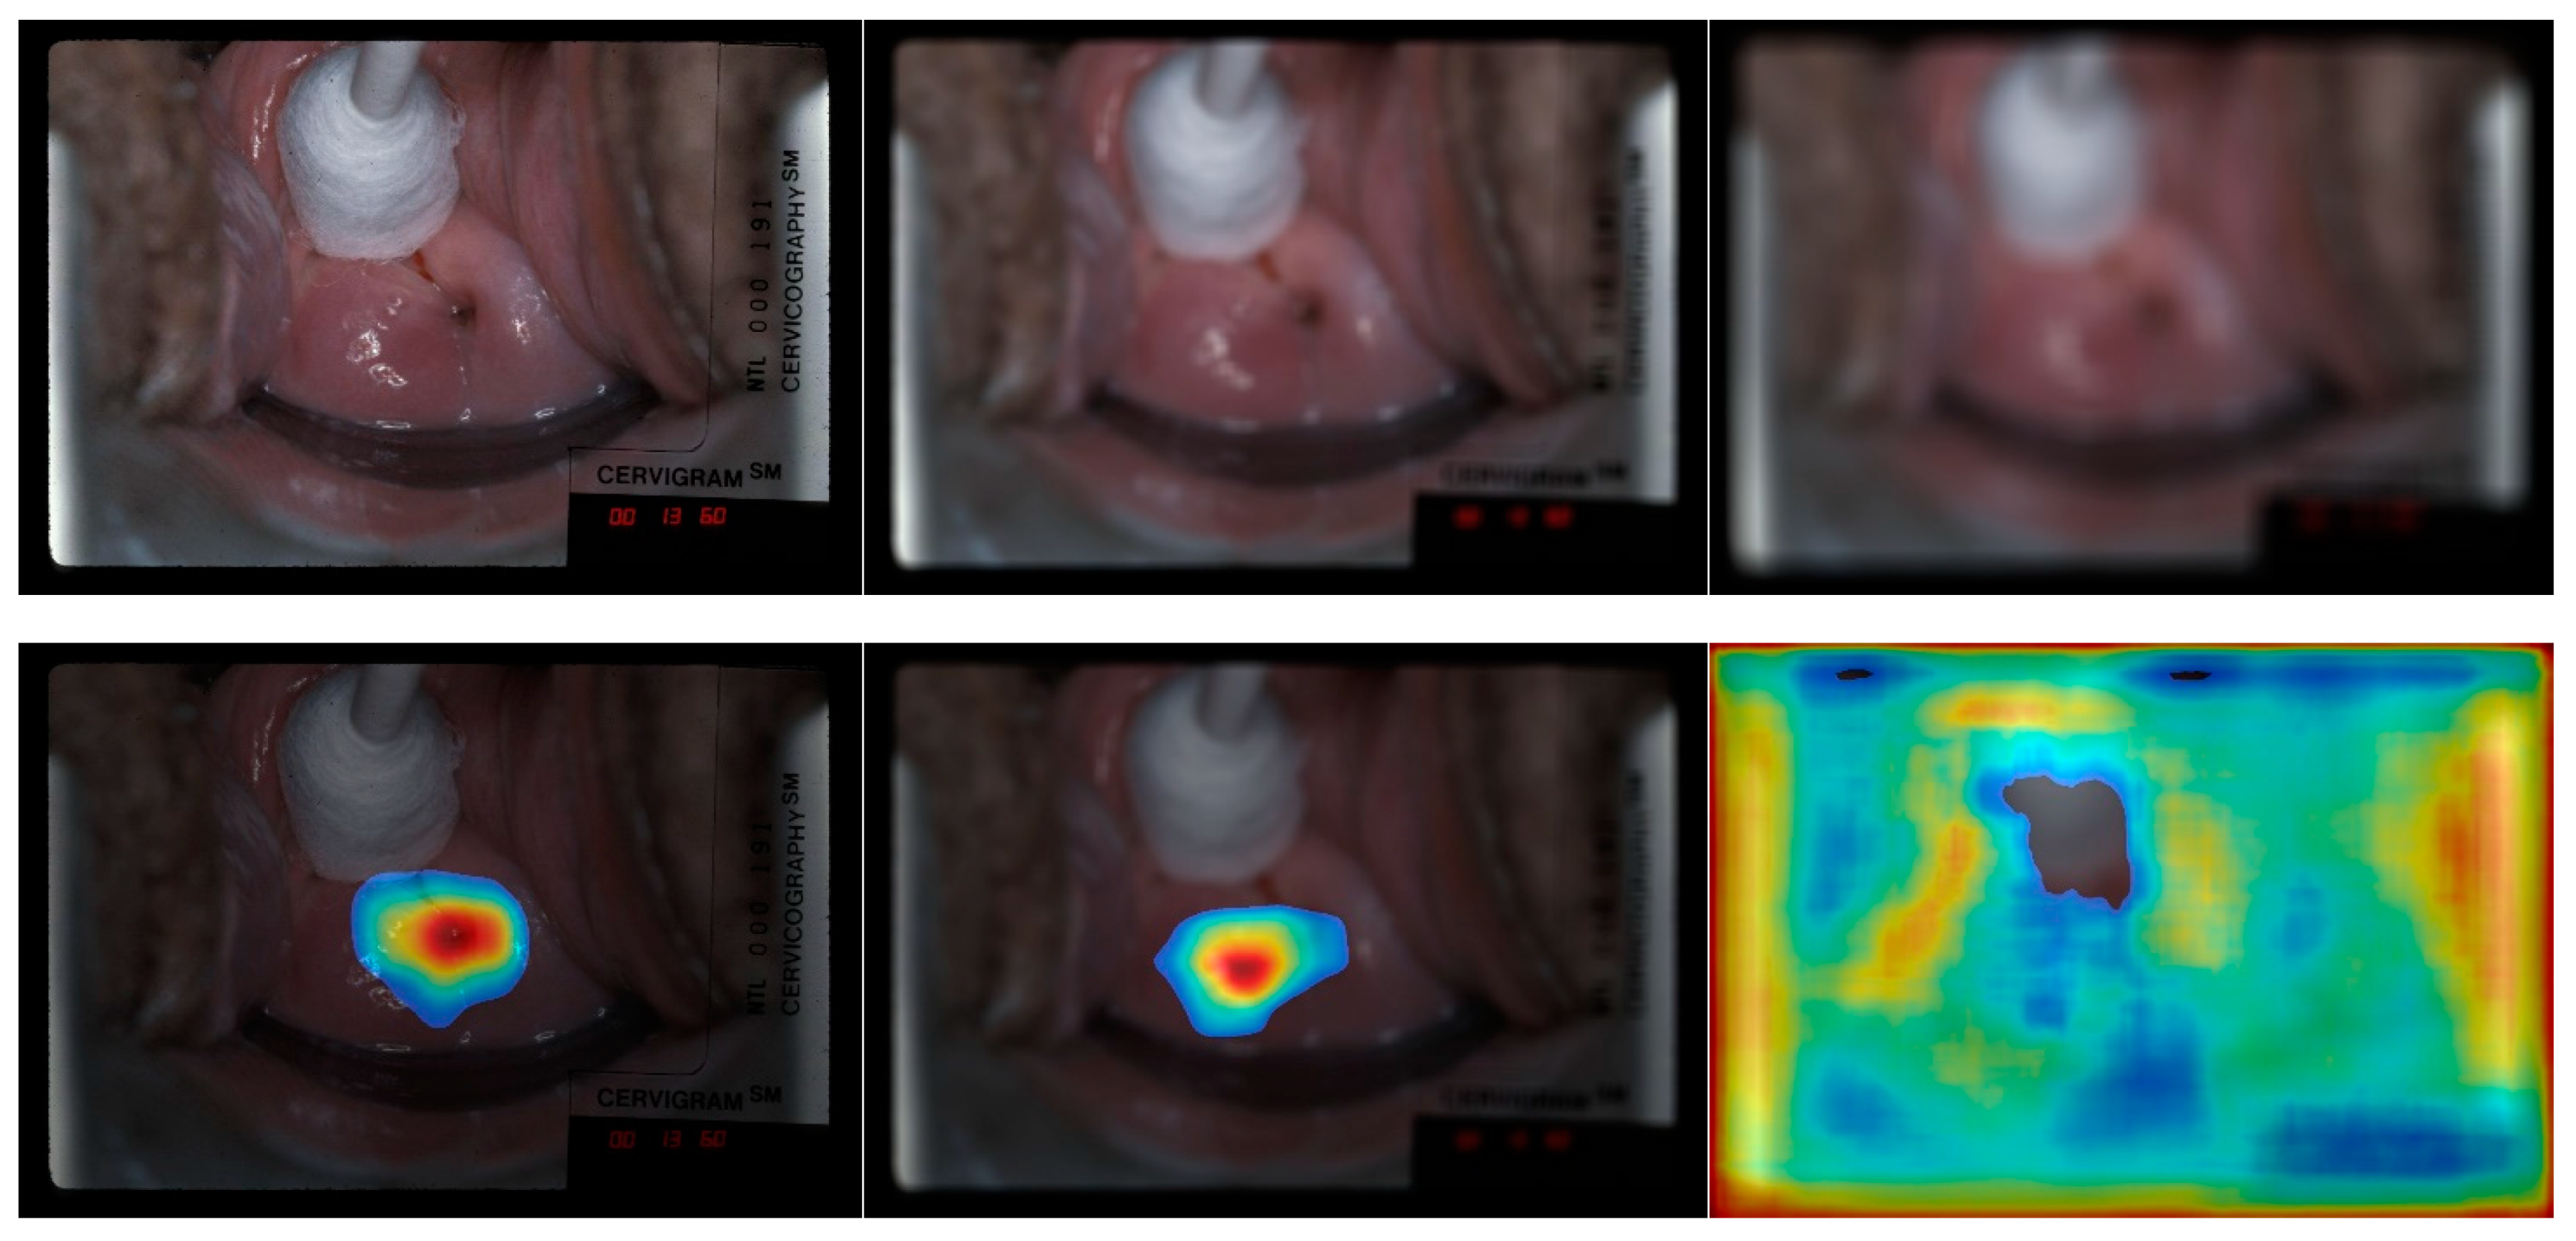

- The heatmaps from both CRM and CAM shows that the most relevant image pixels for making correct classification are those in or around the os and T-Zone.

- Compared to CAM, the CRM (1) visualizes and focuses more on the area around the os and T-zone; and (2) generates fewer heatmaps that the human expert disagrees with.

- Good image/object quality is a key factor to ensure correct classification, and quality degradation can be a huge distractor for capturing significant features and for making correct classifications.

4.4. Quality Degradation